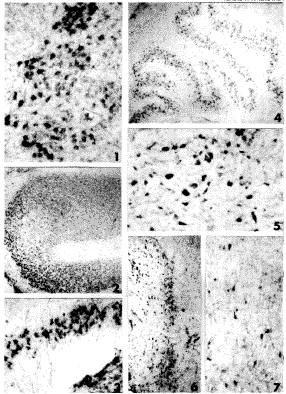

(1)对照pRSV-LacZ转染的骨骼肌细胞经X-gal组织化学染色后呈蓝色,光镜下观察蓝染细胞占骨骼肌细胞总数的10%~20%(图6)。

(2)pCMV-IL2、pRSV-IL2转染的骨骼肌细胞经ABC免疫组织化学染色后,阳性细胞呈褐色,阳性细胞占总数的10%,细胞核深染,含不同启动子的两种质粒的表达情况未见差别(图7,8)。

图6 免疫组织化学方法检测LacZ基因在大鼠原代培养骨骼肌中的表达

Fig.6 Detection of LacZ gene expression in primary skeletal

muscle cell of the rat by immunohistochemical stain.

图7 免疫组织化学方法检测pCMV-IL2在大鼠原代培养骨骼肌中的表达

Fig.7 Detection of pCMV-IL2 expression in primary skeletal

图8 免疫组织化学方法检测pRSV-IL2在大鼠原代培养骨骼肌中的表达

Fig.7 Detection of pRSV-IL2 expression in primary skeletal

Fig.1 NOV mRNA neurons in ventral region of the spinal cord at 16 weeks of gestation age.The strong hybridization signal were localized in the cytoplasm. ×100

Fig.2 NOV mRNA neurons in principal nucleus of inferior olive at 16 weeks of gestation age the density of positive cells were high. ×40

, http://www.100md.com

Fig.3 The density of NOV mRNA in principal nucleus of inferior oliveat 25 weeks of gestation age were lower than that of 16 weeks of gestation age,but the positive signal were stronger. ×100

Fig.4 NOV mRNA neurons were widely distributed throughout the principal nucleus of inferior olive at 28 weeks of gestation age. ×40

Fig.5 NOV mRNA neurons in gracile nucleus at 38 weeks of age.There are three types of positive neurons:large,middle and small in size. ×100

Fig.6 NOV mRNA neurons distributed in striatum at 38 weeks of gestation age. ×40

Fig.7 NOV mRNA neurons localized in Ⅴ and Ⅵ layer of cerebral cortex of parietal lobe were large pyramidal cells. ×100